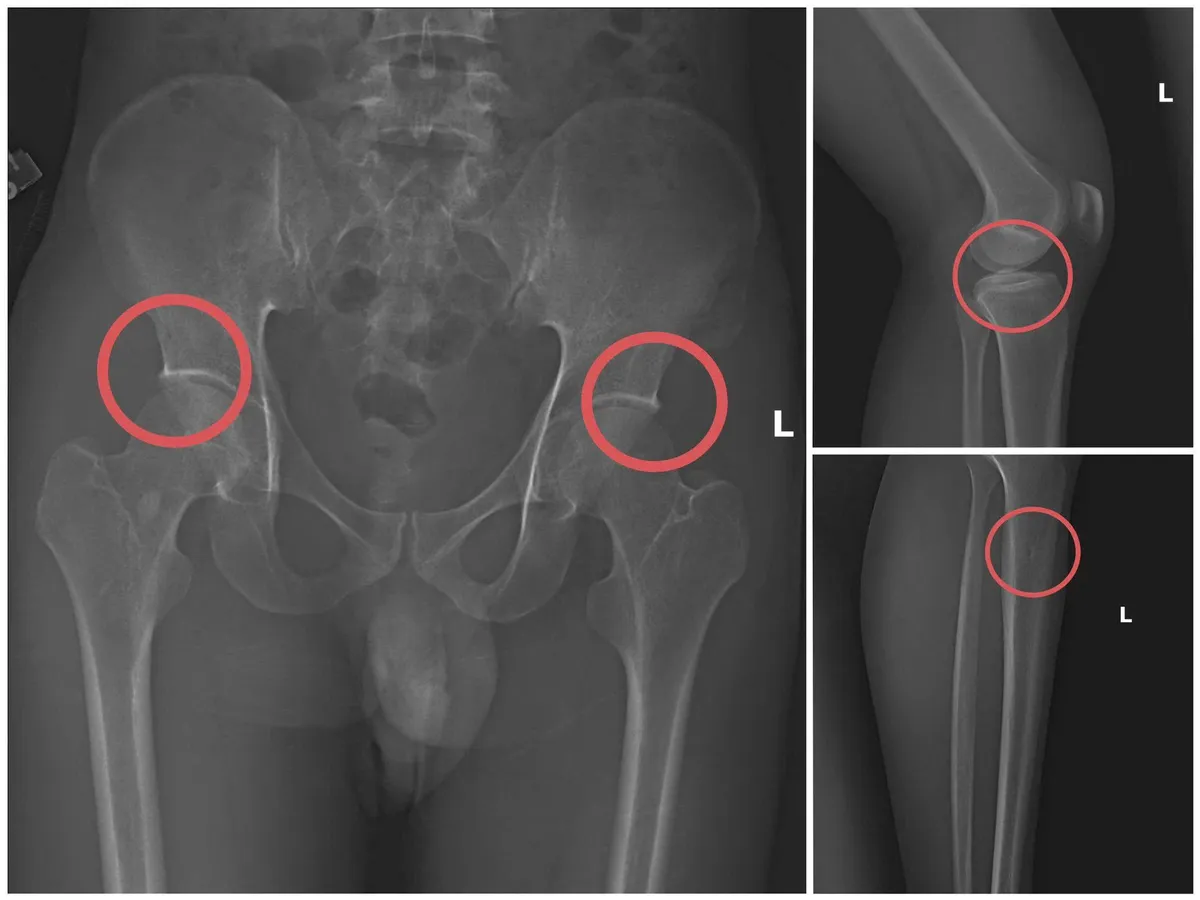

Bản phim chụp XQ một số tổn thương xương do đối tượng tạo ra.

Lợi dụng thời gian dài công tác trong ngành y và am hiểu sâu cấu tạo xương – khớp, cũng như cơ chế chi trả bảo hiểm đối với các thương tích gãy xương giá trị cao, Châu đã dựng lên một quy trình trục lợi bài bản, từ việc vận động mua bảo hiểm, tổ chức gây thương tích, đến hợp thức hóa hồ sơ bệnh án để chiếm đoạt tiền của các công ty bảo hiểm.

Đối tượng Châu trực tiếp thực hiện hành vi tiêm thuốc mê, rồi dùng kim tiêm, búa, định để tác động vào xương người mua bảo hiểm, tạo nên các vết nứt, vỡ xương tương tự tai nạn thật. Khi thương tích đã tạo xong, Châu tiếp tục hướng dẫn các đối tượng dựng hiện trường giả như điện giật ngã, trượt chân ngã suối nhằm hợp thức hóa bệnh án và hoàn thiện hồ sơ yêu cầu chi trả.